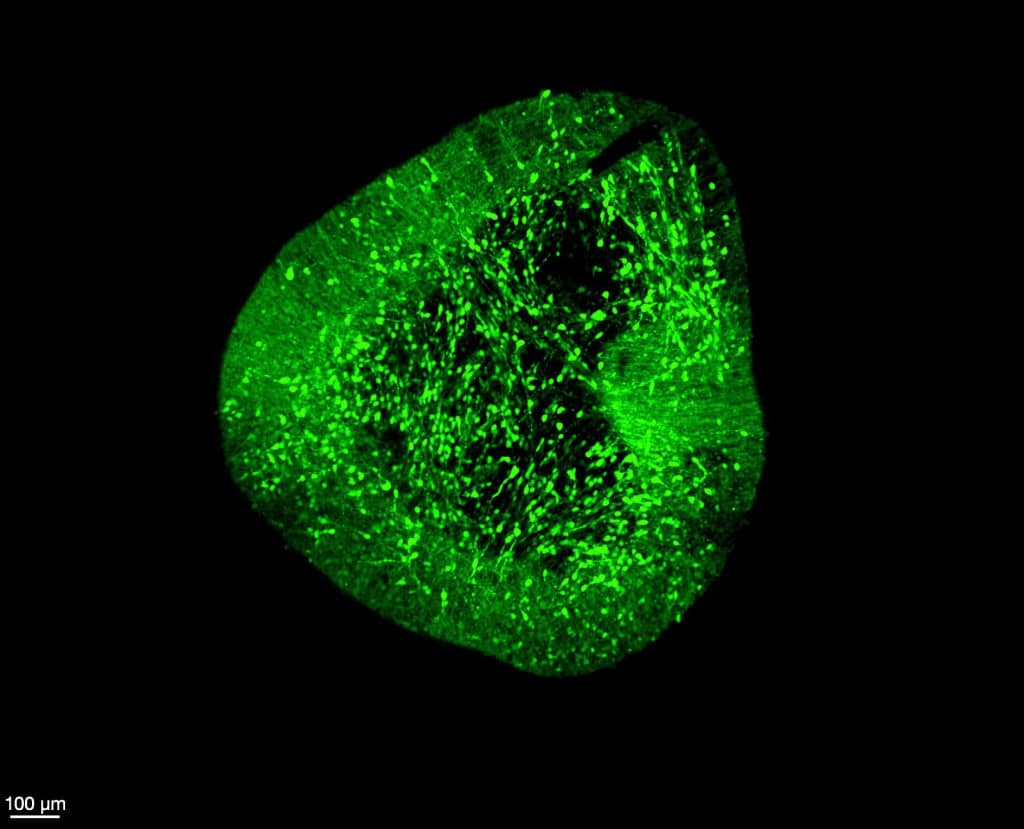

O mapeamento foi criado por meio de uma estrutura batizada de BrainSTEM (Brain Single-cell Two tiEr Mapping), um processo em duas etapas que analisou cerca de 680 mil células do cérebro fetal. A primeira etapa traçou o panorama celular amplo, enquanto a segunda ampliou a resolução especificamente para o mesencéfalo, onde se localizam os neurônios dopaminérgicos — células essenciais para o controle motor e aprendizado, afetadas no Parkinson.

Esse atlas detalhado funciona como um “mapa de referência” que permite comparar a precisão de células produzidas em laboratório com as células reais do cérebro humano. A intenção é garantir maior qualidade na geração de neurônios dopaminérgicos, apontados como promissores para terapias regenerativas destinadas a aliviar sintomas como tremores e perda de mobilidade.